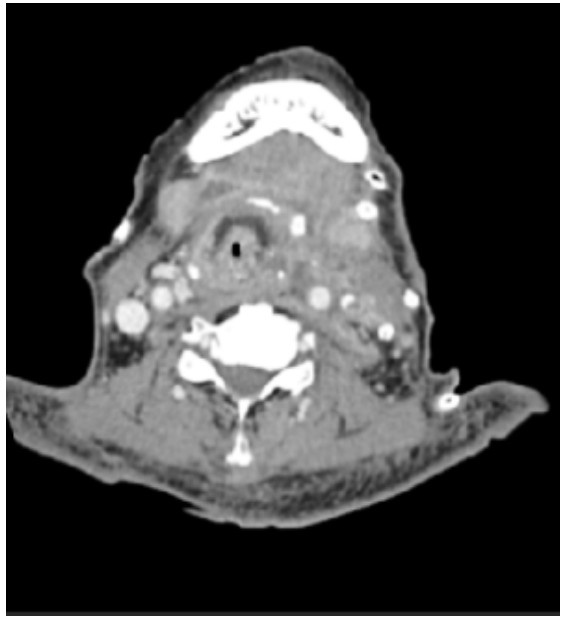

入院后,立即予以保护性气管插管,机械通气辅助呼吸,去甲肾上腺素0.03 µg/(kg·min)维持血压,实时液体复苏;注射用美罗培南0.5 g每8 h一次抗感染治疗,输注血小板和血浆纠正血小板减少。入院第2天,患者血液动力学不稳定,血小板危急值,手术出血风险高,故在充分风险告知的情况下,超声引导下先行颈部脓肿穿刺切排,置管引流。入院第3天,患者血小板计数65×109/L,继续输注血小板治疗,头颈部CT(图 2)示:左侧颌面部、颌下区、咽旁间隙及颈部软组织感染伴脓肿形成,局部病变增大。脓液二代测序(next generation sequencing, NGS)检测提示链球菌(26061),化脓拟杆菌(11504), 普雷沃菌(17803)等感染,予加用利奈唑胺葡萄糖注射液0.6 g每天2次抗感染治疗。入院第4天,患者呕血50 mL,解棕色糊状便,气管痰液多,予内镜下留置鼻肠管,气管镜下吸痰。入院第5天,血小板上升至181×109/L,急诊全麻下行口腔颌面部、咽旁间隙、颈深部脓肿切排引流术+皮瓣转移修复术,术中予PVP-Ⅰ、生理盐水反复清洗脓腔后在咽旁、颏下、颈鞘各置入引流管1根进行脓腔引流。入院第7天,痰培养提示鲍曼不动杆菌阳性,根据药敏结果改用注射用头孢哌酮钠舒巴坦钠2.0 g每12 h一次抗感染治疗。入院第8天,患者气管插管拔管困难,予局麻下行气管切开术。入院第9天,患者顺利脱机,血液动力学稳定,炎症指标下降,由EICU转回普通病房。入院第13天复查咽喉部增强CT(图 3)示:口腔颌面部、咽旁间隙、颈深部脓肿切排引流+皮瓣转移修复术后,脓腔较前缩小;入院第21天,患者体温正常,感染控制,顺利出院。

| 图 2 头颈部增强CT(轴位) |